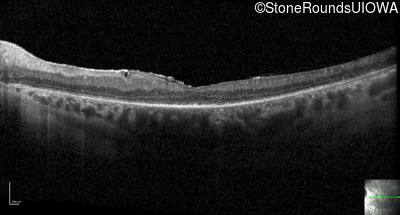

Optical Coherence Tomography - Right - 20/100 -2

Exemplar / OCT Stack

OCT Stack